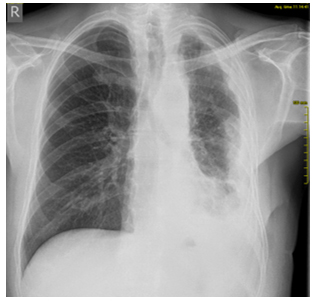

was diagnosed. On the follow-up PA chest radiograph from 16.09.2018.

(Figure 2), the left hemidiaphragm and left costophrenic angle are

obscured by a laterally ascending shadow—pleural effusion is

present. The remaining part of the lung parenchyma on the left shows

reduced transparency.

Figure 2. Control radiography of the chest